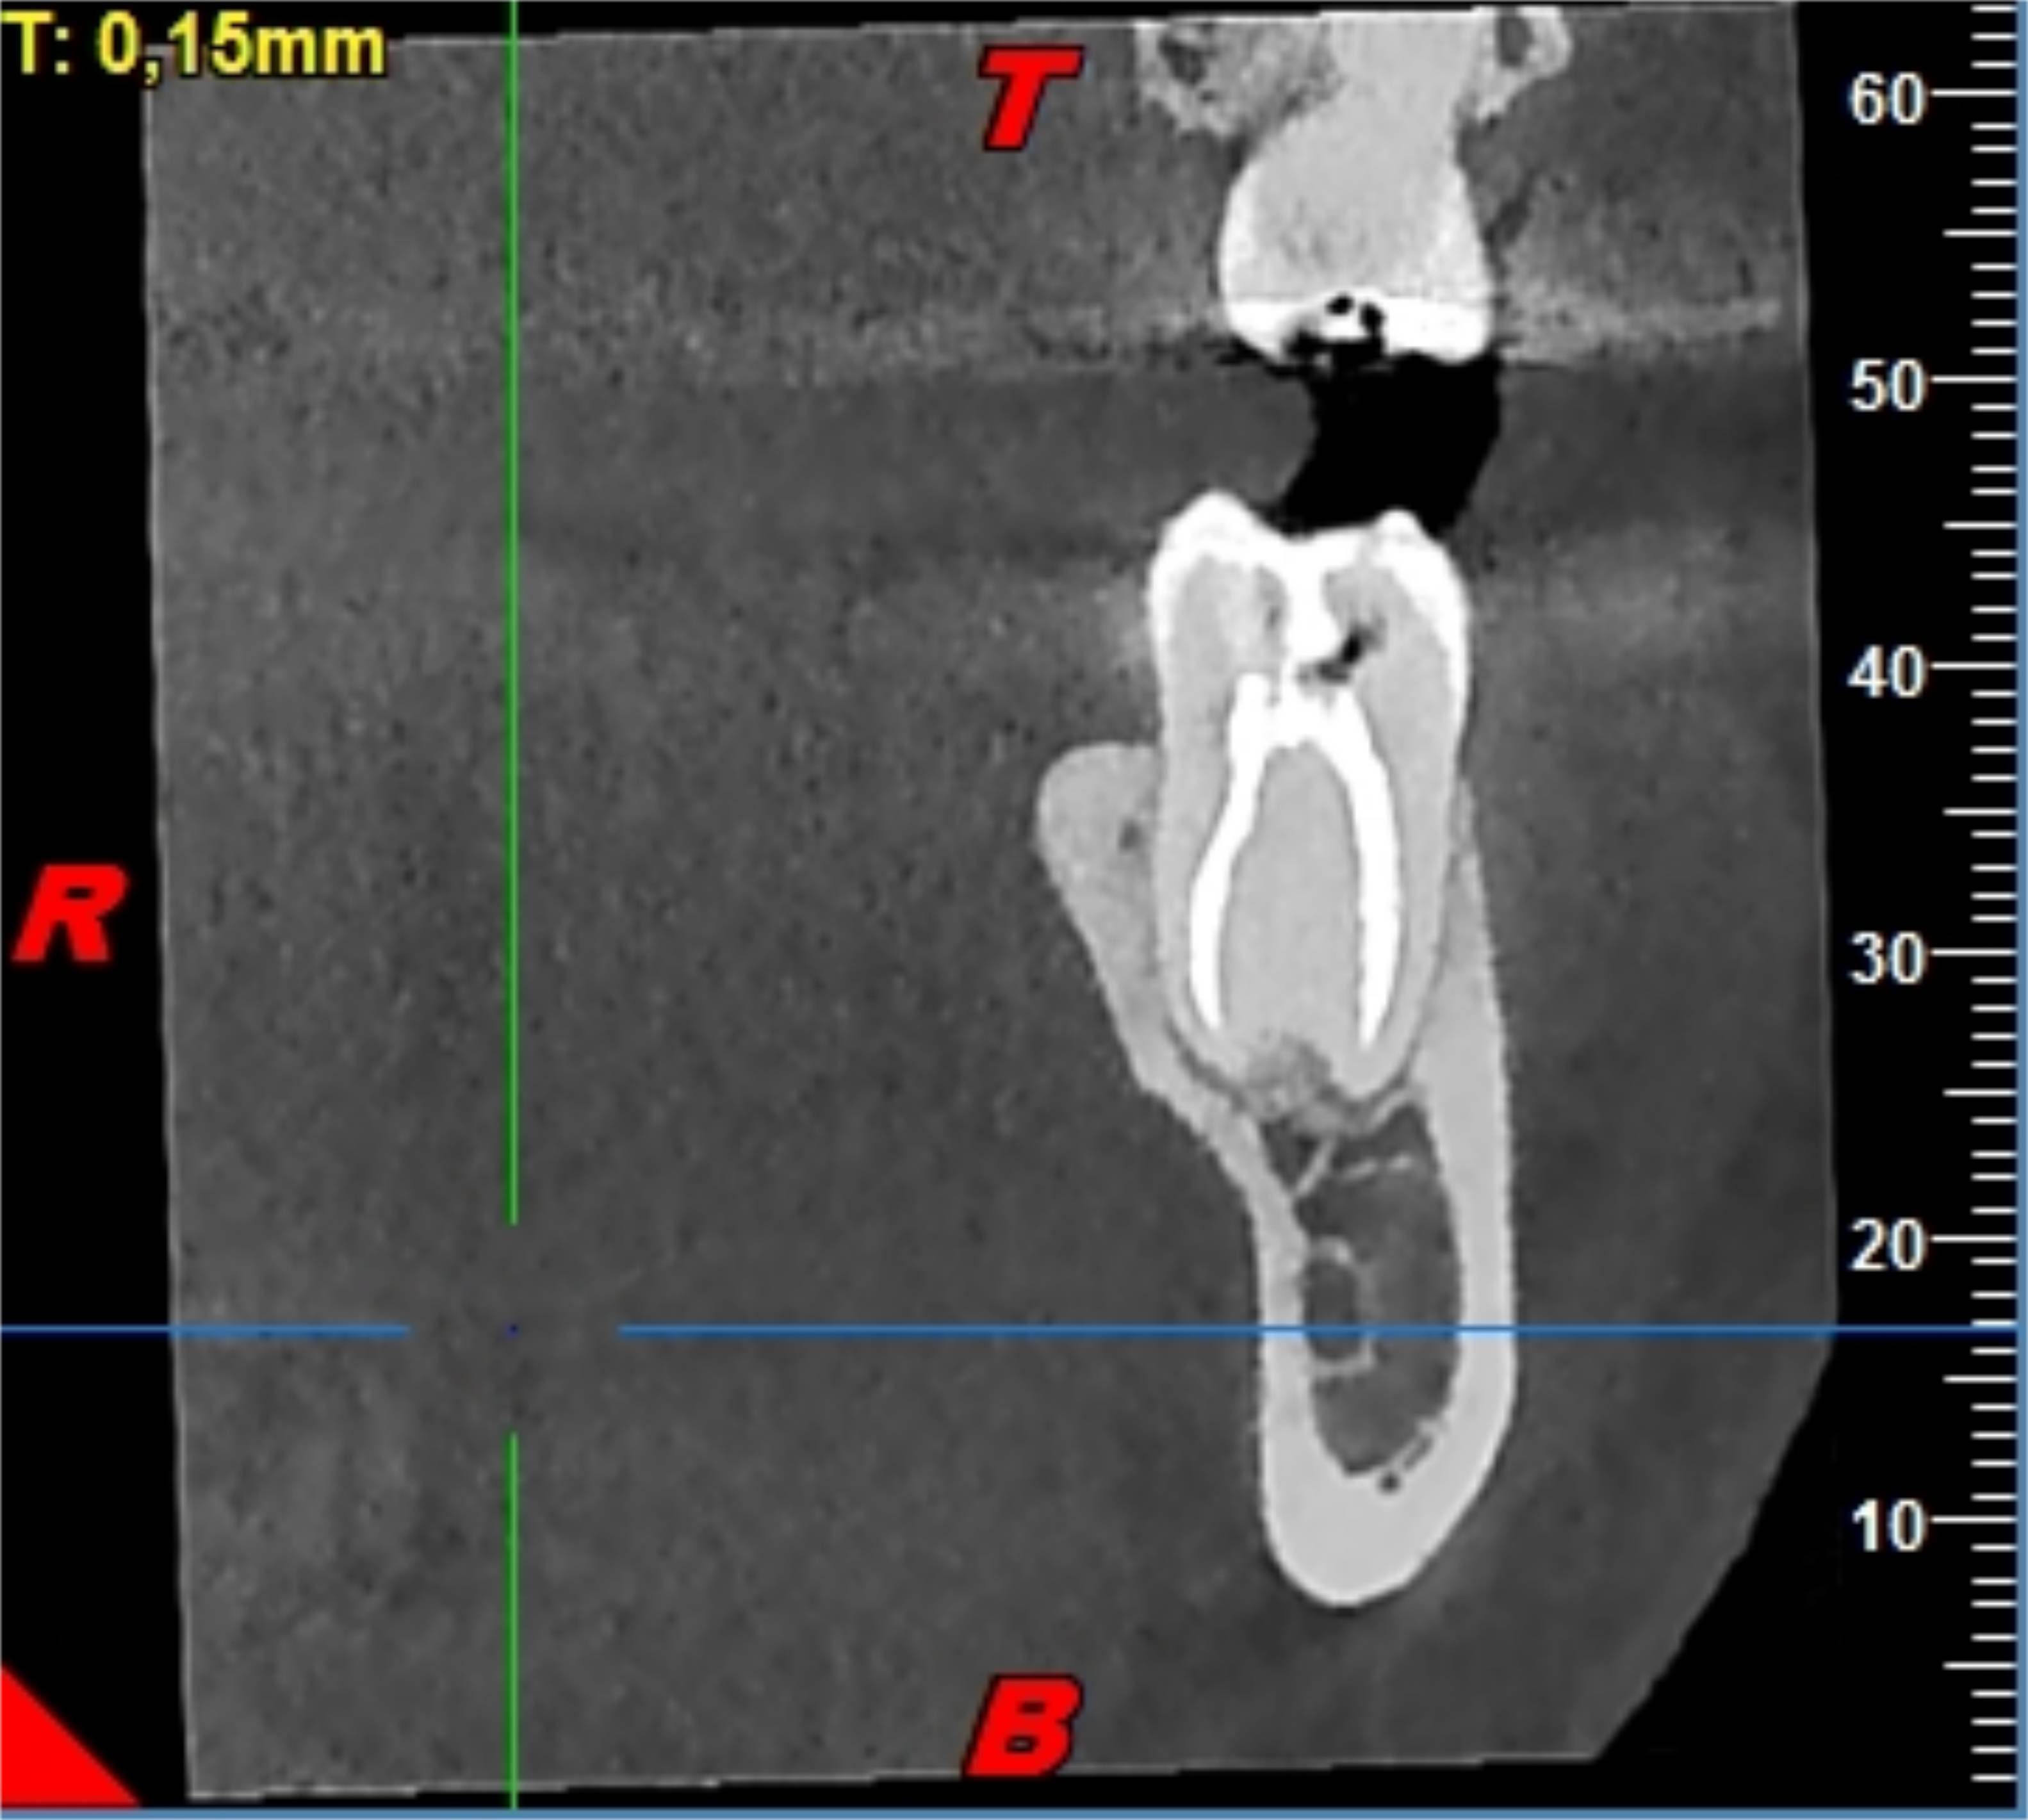

Resulta especialmente indicado para la evaluación de lesiones apicales, planificación en tratamiento de dientes fracturados o fisurado, lesiones en la cámara pulpar y de los conductos radiculares, tanto en número como en relleno de material de obturación.Los distintos tamaños de FOV permiten reducir la exposición a la radiación del paciente, limitándola a la zona de interés.

El objetivo de este estudio es ofrecer la visión más amplia de la pieza a tratar. Se realizan diferentes tipos de cortes, llegando a un grosor mínimo de 0,125mm en todos los planos posibles.